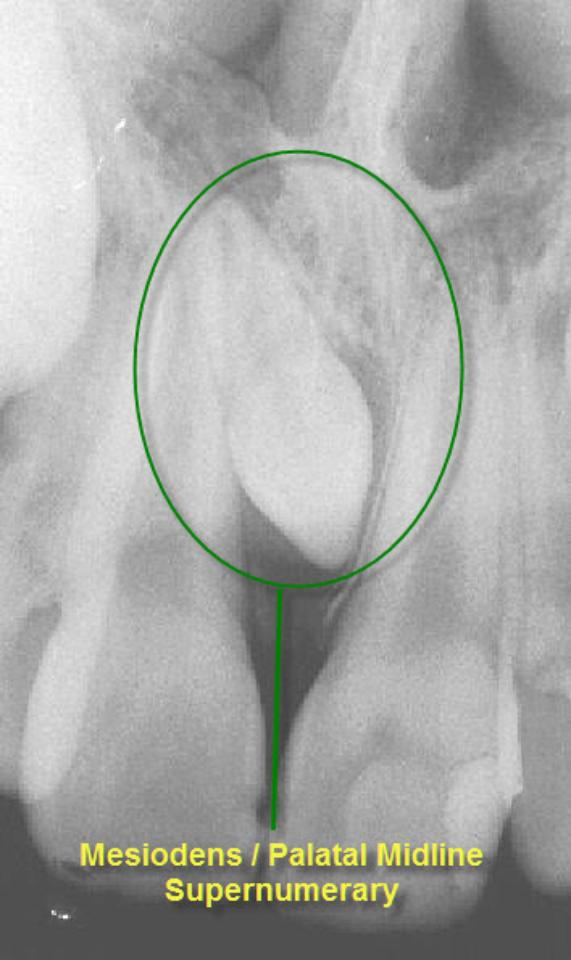

The prevalence of supernumerary teeth is reportedly between 0.15 – 3.9%. Most commonly, extra teeth are found between the upper central incisors (mesiodentes) or in the region of the premolars (paramolars) or very occasionally, behind the wisdom teeth (distomolars).

80 – 90% of all supernumerary teeth occur in the upper jaw. Half are found at the ‘front’ of the upper jaw. Mesiodentes frequently interfere with the eruption and alignment of the upper incisors. They can delay or prevent eruption, displace or rotate the erupting central incisors or less commonly, ‘bend’ (dilaceration) the developing roots of the central incisors so that tooth eruption is slowed / stopped, ‘eat away’ (resorption) the surrounding teeth, develop cysts around the crowns of the extra teeth (dentigerous cyst formation) and loss of tooth vitality. Rarely, the mesiodens can erupt into the nasal cavity